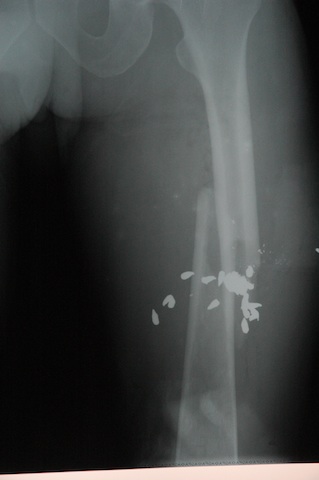

Medical 8-05 to 6-06

Image Date: 11/27/05 4:17:53 AM PST